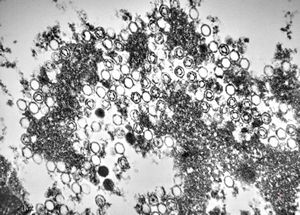

M,50y. | Pneumocystis carinii

M,3m. | Pneumocystis carinii